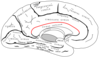

Corpus Callosum

- It is the largest white matter structure in the human brain

- wide, thick nerve tract, consisting of a flat bundle of commissural fibers

- beneath the cerebral cortex in the brain

- only found in placental mammals

- It spans part of the longitudinal fissure, connecting the left and right cerebral hemispheres, enabling communication between them

- four main parts; individual nerve tracts that connect different parts of the hemispheres. These are the rostrum, the genu, the trunk or body, and the splenium

Relations of Corpus Callosum

- fibers radiate in the white matter and pass to the various parts of the cerebral cortex

- those curving forward from the genu into the frontal lobes - forceps minor

- those curving backward from the splenium into the occipital lobes - forceps major (also forceps posterior)

tapetum - main body of fibers between these two parts

Commissura fornicis

- commissural fiber

- a C-shaped bundle of nerve fibers in the brain that acts as the major output tract of the hippocampus

- also carries some afferent fibres to the hippocampus from structures in the diencephalon and basal forebrain

- The fornix is part of the limbic system